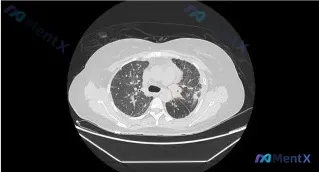

ALK-TKI治疗11个月后左肺上叶病灶进展,是耐药还是更凶险的情况?

整理了一个有意思的病例,核心是ALK-TKI靶向治疗11个月后CT提示进展,影像表现和病史结合起来有几个容易踩坑的点,分享一下我的分析思路。

- 本次影像(胸部CT肺窗):

- 主要病灶:左肺上叶,混合磨玻璃影(GGO背景+实性成分),密度不均

- 恶性相关征象:支气管结构部分掩盖/扭曲、局部管腔狭窄、左侧胸膜牵拉/凹陷、左肺门区紧邻纵隔处密度增高影(可疑淋巴结/肺门增粗)

- 其他背景:双肺散在少量条索影(陈旧/慢性炎症可能),无明显肋骨破坏或胸壁肿块